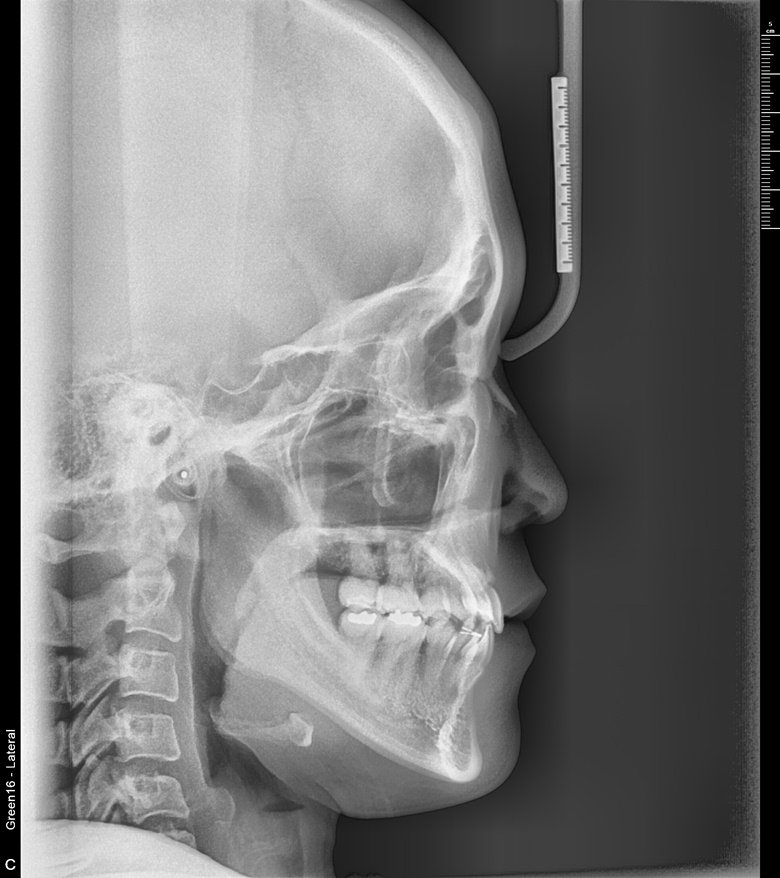

치료 후 사진입니다.